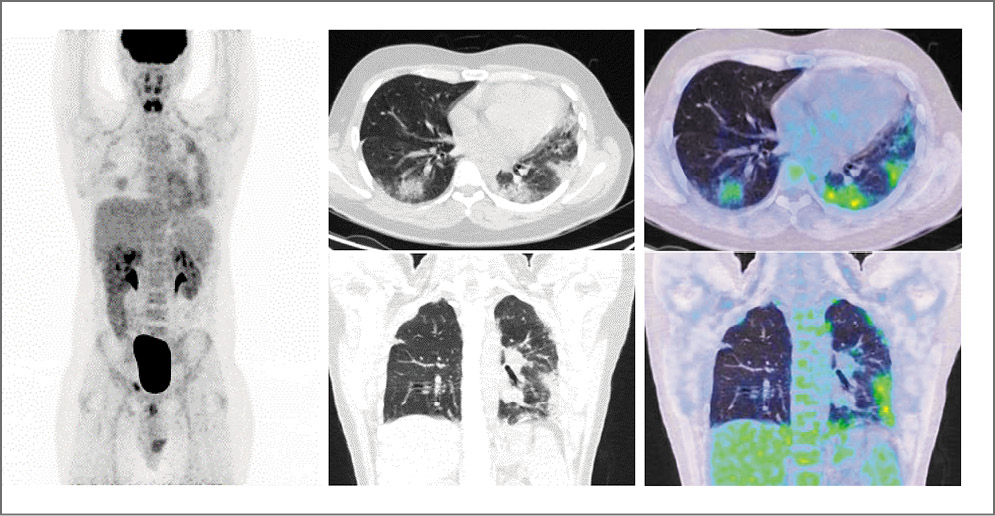

Больной О., 44 года. По поводу рака правого яичка выполнена орхифуникулэктомия. При гистологическом исследовании – эмбриональный рак с элементами тератомы. По данным СКТ органов грудной клетки выявлены множественные метастазы в легкие максимальным размером до 31 мм, в средостении определяются паратрахеальные лимфоузлы размерами 36×27 мм. При СКТ органов брюшной полости определены метастазы в забрюшинные лимфоузлы в виде конгломерата размерами до 120×38 мм. Уровень хорионического гонадотропина человека – 448 мЕд/мл, альфа-фетопротеина – 1305 МЕ/мл, лактатдегидрогеназы – 278,4 ЕД/л. Установлен диагноз: эмбриональный рак правого яичка, стадия IIIС рT3N3M1вS2. На междисциплинарной комиссии назначена системная полихимиотерапия по схеме BEP – 30 мг блеомицина в 1, 3, 5-й дни, 100 мг/м2 этопозида в 1–5-й дни и 20 мг/м2 цисплатина в 1–5-й дни в количестве 4 циклов с учетом факторов прогноза. После 1-го цикла лечения и на протяжении последующих развивалась фебрильная нейтропения. Проводилась поддерживающая терапия Г-КСФ. Оценка эффекта лечения не проводилась. После лечения через 2 нед у больного появились сильная слабость, сухой непродуктивный кашель, одышка в покое, усиливающаяся после физической нагрузки.

Выполнена ПЭТ/КТ с 18F-ФДГ. В легких с двух сторон в базальных отделах субплеврально определяются интерстициальные изменения по типу матового стекла с диффузной фиксацией радиофармпрепарата, SUVmax=1,48 (рис. 2).

Рис. 2. Пациент О., 43 года. На ПЭТ, аксиальных и корональных ПЭТ- и КТ-проекциях в легких с двух сторон в базальных отделах субплеврально определяются интерстициальные изменения по типу матового стекла с диффузной фиксацией радиофармпрепарата (SUVmax=1,48).